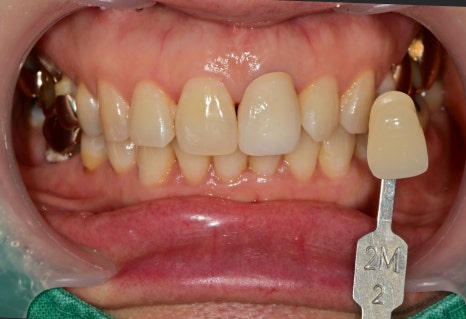

치아 색 맞추는 단계

어둡게 비추는 부분을 커버하기 위해

여러 색을 대조해 보고 수정을 하는 과정이 필요했습니다.

앞니 심미보철을 제작할 경우에는

하나의 치아를 주변 기존 치아에 맞춰서 제작하는 것은

주변 조건을 다 충족시키기 어렵고 분명 한계는 존재합니다.

다행히 주변 치아들의 캐릭터가 평범했기 때문에

좋은 결과물이 나올 수 있었던 것 같습니다.

전후 사진 비교

이렇게 앞니의 보철치료는

기능적 뿐만 아니라 심미적인 요인도

작용하기 때문에 치료 결정에는

여러 요인이 작용하는 부분입니다.